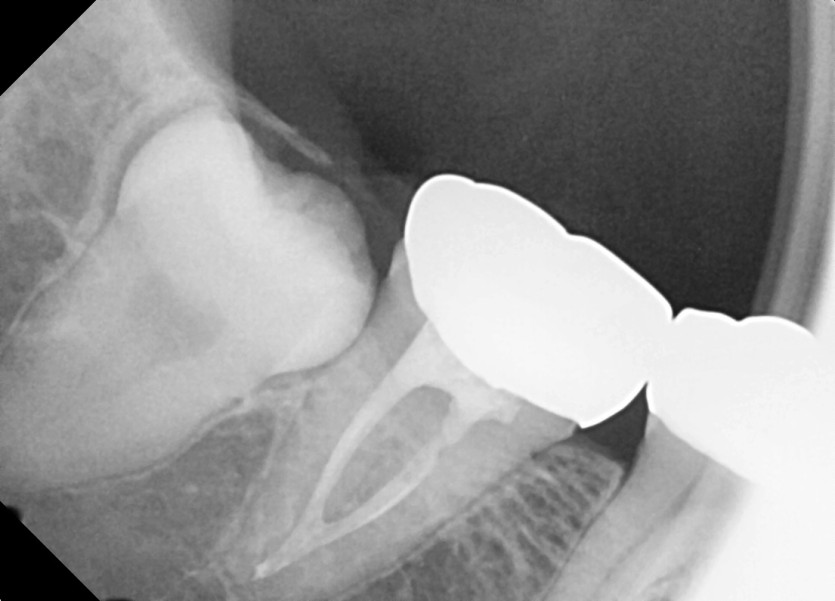

#48 사랑니 발치

구강 외과 전문의가 당일 발치했습니다.